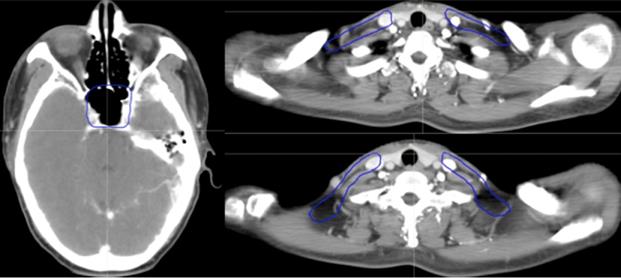

Figure 3

Selected computed tomography slices to demonstrate the delineation of different risk target volumes. Red: PGTVnx; yellow: PGTVnd; green: PTVnx; pink: PTVna; blue: PTV1. Abbreviations: PGTVnx: planning target volume of nasopharyngeal GTV; PGTVnd: planning target volume of GTV in cervical lymph nodes; PTVnx: planning target volume of nasopharynx; PTVna: planning target volune of neck area; PTV: planning target volume 1.

Figure 2

Figure 4

Selected computed tomography slices to demonstrate the delineation of low-risk target volumes. Red: PGTVnx; yellow: PGTVnd; green: PTVnx; pink: PTVna; blue: PTV1. Abbreviations: PGTVnx: planning target volume of nasopharyngeal GTV; PGTVnd: planning target volume of GTV in cervical lymph nodes; PTVnx: planning target volume of nasopharynx; PTVna: planning target volume of neck area; PTV: planning target volume 1.